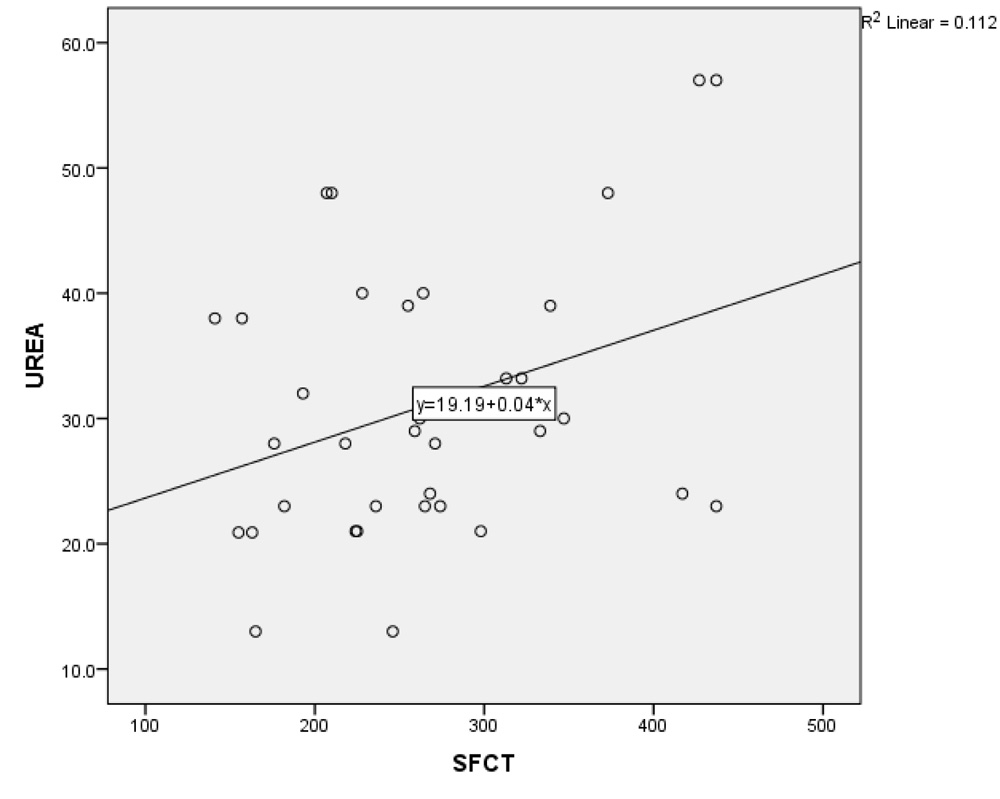

In NPDR group, there was no significant correlation between CT and creatinine (p = 0.2), urea (p = 0.17) and HbA1C levels (p = 0.71). However, in the PDR group, there was significant positive correlation between increasing levels of both creatinine & urea with SFCT (p=0.01 & p=0.04 respectively). (Table 2 and 3; Graph 1 and 2), while no correlation existed with HbA1C levels.

Graph 2: Correlation between changes in subfoveal choroidal thickness with blood urea levels in PDR group